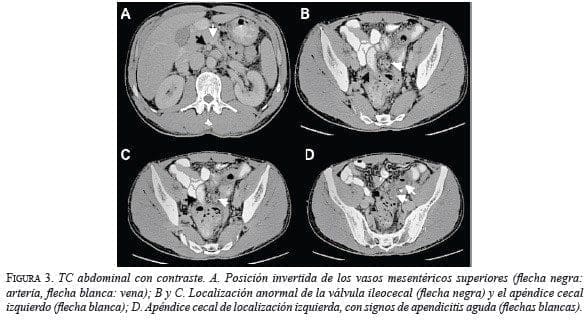

En el examen de ecografía abdominal total se observó íleo inespecífico. La TC demostró malrotación intestinal, sin situs inversus, con asas intestinales delgadas que ocupaban el hemiabdomen derecho y el colon en el hemiabdomen izquierdo. El ciego estaba en posición anómala, en el espacio presacro, ejerciendo leve compresión sobre el recto, el cual se desplazó hacia la izquierda. Dependiente de este, en la fosa iliaca izquierda se observó un asa tubular ciega con un diámetro de 18 mm, distendida por líquido y con cambios inflamatorios de la grasa adyacente, correspondiente al apéndice cecal. Además, se observó posición anatómica invertida de los vasos mesentéricos superiores, o sea, la arteria a la derecha y la vena a la izquierda (figuras 2 y 3).